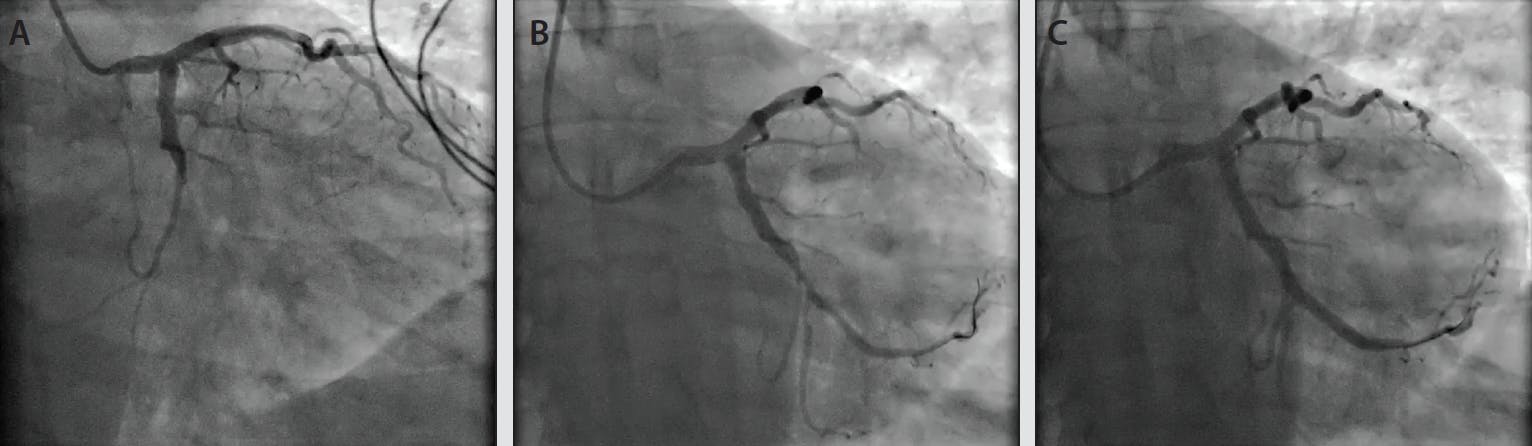

Figure 4 and Figure 5 showcase two cases from our experience that demonstrate the benefit of frontline utilization of CAT RX. In the first case (Figure 4), balloon angioplasty was used prior to CAT RX. Distal embolization caused by the initial balloon inflation potentially limited the ability to achieve TIMI 3 flow. In the second case (Figure 5), CAT RX was used frontline. After one pass of CAT RX there was clear visualization of the underlying lesion, a stent was placed, and TIMI 3 flow was achieved with myocardial perfusion normalization.

Figure 5. A male patient in his early 40s presenting with occlusion of the left circumflex artery (A). Postprocedure image after one run of CAT RX (B). Final result with TIMI 3 flow and myocardial perfusion normalization (C).